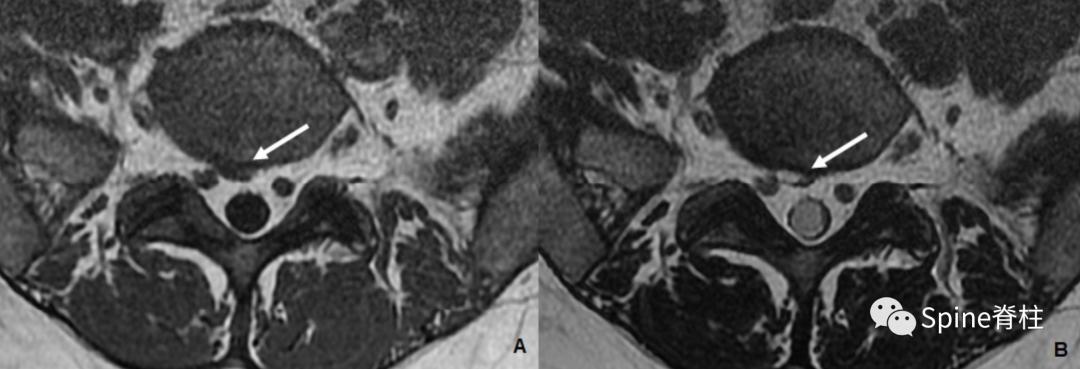

二、椎间盘囊肿 (discal cyst)

椎间盘囊肿是一种罕见的与邻近的椎间盘相通硬膜外囊肿。在MRI上,表现为附着在椎间盘上的腹外侧、硬膜外的囊性肿块,增强后囊壁边缘可见强化。有时,病变可累及至侧隐窝。一般认为其由创伤性纤维环撕裂引起的液体积聚而形成的假性囊肿,其临床症状与椎间盘突出症或其他脊柱囊肿患者难以区分。组织学上,椎间盘囊肿与其他囊肿的主要区别在于椎间盘囊肿壁中缺少内皮细胞。

一名40岁患者的腰椎MRI提示L5/S1椎间盘囊肿(箭头),右侧S1神经根无明显受压。图A是T1加权像;图B为T2加权像